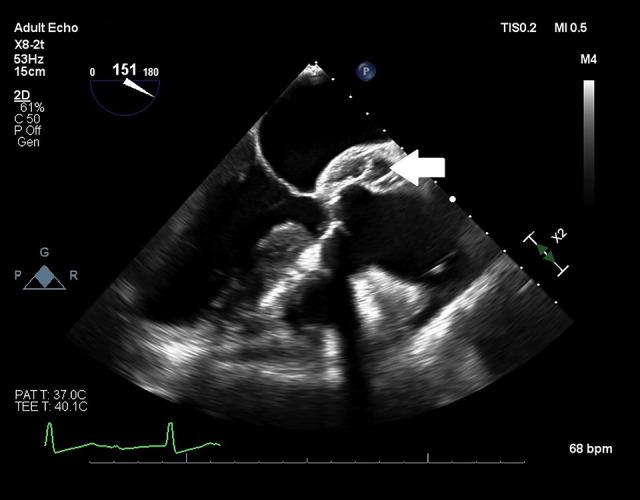

BACKGROUND Aorto-atrial fistulas (AAFs) are rare lesions typically associated with paravalvular abscesses or aortic aneurysms. Iatrogenic AAFs have been described after cardiac surgery. While these lesions are often asymptomatic, they can cause shunting and volume overload. Diagnosis of AAFs can be challenging. Transesophageal echocardiography plays a critical role in their diagnosis. CASE REPORT A 91-year-old man undergoing transcatheter aortic valve replacement (TAVR) for severe aortic stenosis had extreme tortuosity of the aorta and iliofemoral vessels. The patient developed a fistula from the non-sinus of Valsalva to the right atrium during the procedure. After the procedure, the patient developed stroke and retroperitoneal hematoma. CONCLUSIONS This case represents the first full report of an aorta to right atrial fistula after TAVR. The anatomy of the aortic root in relation to the right atrium and ventricle may make aorta to right ventricle fistulas more common than aorta to right atrial fistulas. This patient's vascular tortuosity may have played a role in the development of this lesion. Blood flow in an aorta to right atrial fistula occurs during both systole and diastole, making both right and left ventricle overload possible. Echocardiography is essential to the diagnosis of these lesions. Both vascular injury and landing zone rupture are possible during TAVR, although the observed timing and anatomy of this lesion suggest that it was caused during retrograde access of the left ventricular outflow tract via the ascending aorta.

摘要

主动脉-心房瘘(AAFs)是一种罕见的病变,通常与瓣周脓肿或主动脉瘤有关。医源性 AAFs 已在心脏手术后被描述。虽然这些病变通常无症状,但它们会导致分流和容量过载。AAF 的诊断具有挑战性。经食管超声心动图在其诊断中起着关键作用。

病例报告

一名 91 岁男性因严重主动脉瓣狭窄而行经导管主动脉瓣置换术(TAVR),其主动脉和髂股血管极度迂曲。在手术过程中,患者从非窦 Valsalva 到右心房出现瘘管。手术后,患者发生中风和腹膜后血肿。

结论

本例是 TAVR 后首例完全报告的主动脉-右心房瘘。主动脉根部与右心房和心室的解剖结构可能使主动脉-右心室瘘比主动脉-右心房瘘更常见。该患者的血管迂曲可能在该病变的发展中起作用。主动脉-右心房瘘中的血流在收缩期和舒张期都发生,这使得右心室和左心室都有可能过载。超声心动图对于这些病变的诊断至关重要。虽然观察到的病变时间和解剖结构提示它是在通过升主动脉逆行进入左心室流出道期间引起的,但在 TAVR 期间可能会发生血管损伤和着陆区破裂。